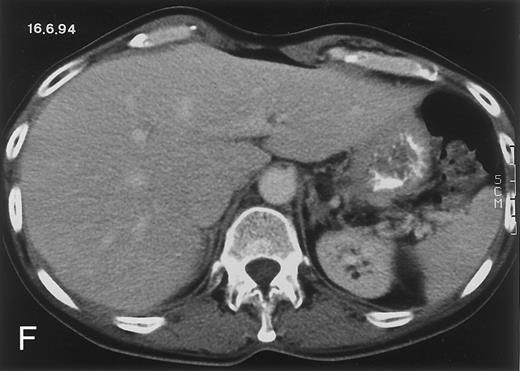

(D) On August 23, 15 days after the neutrophil count had dropped below 500/μL in the third chemotherapy cycle, focal liver lesions clearly decreased in size and number. (E) On September 30, 35 days after neutrophil recovery, multiple hepatic abscesses are seen (arrowhead). To show maximal extent of lesions the scan shown is at a slightly different level. (F) On June 16, 1994, 230 days after neutrophil recovery, the CT scan has normalized.

Evolution of fungal lesions on CT scans during and after neutropenia is summarized in Table 2. Figure 1 (patient A) and Fig 2 (patient B) serve to illustrate Table 2.

In three patients, multiple round lesions were seen on postcontrast CT scans of the abdomen in the liver and the spleen, while in two cases, lesions could only be seen in the liver (Table 2). Following the diagnosis of disseminated candidiasis, these lesions decreased in size and visibility during subsequent neutropenia in three patients (compare Fig 2A and B) and disappeared completely in two patients (compare Fig 1A and B). The numbers of days of severe neutropenia (neutrophils <500/μL) at the time the CT scan was performed are listed in Table 2. After recovery from neutropenia and despite continued antifungal therapy, the size and visibility of the lesions increased again (Fig 1C). Similarly, the number of days since recovery from severe neutropenia (neutrophils >500/μL) are listed in Table 2. In two of three patients treated with another cycle of myeloablative chemotherapy, this waxing and waning pattern of radiologic lesions could be seen again (Fig 1D and E). In all patients, lesions eventually disappeared (Figs 1F and 2D) after prolonged antifungal therapy.